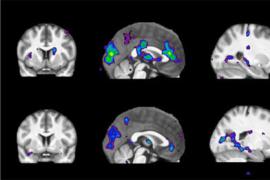

Когда речь идет о разработке новых способов диагностики болезни Альцгеймера, ученые в первую очередь сосредотачивают свое внимание на структуре головного мозга. Однако исследователи из Университета Тель-Авива (Tel Aviv University), Израиль, убеждены, что исследовать необходимо не структуру, а метаболизм головного мозга.

«На самых ранних стадиях болезни, задолго до появления первых внешних симптомов, в метаболических процессах головного мозга происходят первые изменения, — пишет в журнале Neurobiology of Aging автор исследования Шири Стемплер (Shiri Stempler) с медицинского факультета университета. — Поэтому мы разработали модель, предсказывающую развитие болезни Альцгеймера по определенным биомаркерам, которые можно получить с помощью обычного анализа крови. Точность предсказания составит до 90 процентов».

Исследователи обратили свое внимание на гиппокамп — структуру головного мозга, которая отвечает за память и обучение. Именно эта область наиболее поражается при прогрессировании болезни Альцгеймера. Ученые проанализировали метаболические гены, обнаруженные в нейронах гиппокампа и окружающей ткани, и из 1,5 тысячи генов отобрали 50 генов, претерпевающих наиболее характерные изменения. После этого ученые сравнили характеристики этого набора генов у здоровых людей, пациентов с болезнью Альцгеймера и приматов (шимпанзе и макак резус) и выяснили, что во всех группах, кроме больных пациентов, количество этих генов более-менее стабильно. Тогда как у пациентов с болезнью Альцгеймера этих генов либо заметно больше, либо ощутимо меньше. На основе этого анализа была создана модель, которая расценивает любые отклонения в количестве этих генов как сигнал о начале заболевания.